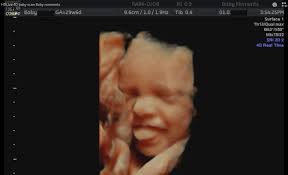

4d ultrasound is a 3d with the time aspect live video of the record. How your baby grows in pregnancy. A 4d ultrasound generates an image that is continuously updated much like a moving image. It is best to think of it with an example.

The main difference is that 3d focuses on the visual effects whereas 4d adds a tangible or tactile aspect to your movie experience. In 4d 3 4 images are taken per second which gives you an illusion of a movie. Or drops of water land on you when iron man flies by the bay. Difference between 3d and 4d images the four dimensional cube tesseract is one example of how the three dimensional world described by x y and z can extend into a fourth one.

3d and 4d ultrasound. A car has three dimensions. A 4d movie is a 3d movie with additional effects providing a real life experience emitted in special cinemas. 3d images are used to show you three dimensional external images that may be helpful in diagnosing issues such as a cleft lip.